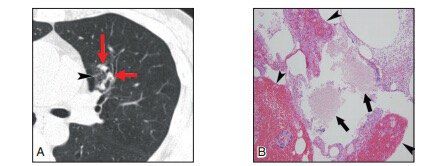

通常表现为中心实性伴周围GGO(CT晕征)。CT晕征代表了与梗死相关的肺泡出血。曲霉菌感染有多种类型,只有血管侵袭性曲霉菌病可表现为GGO的肺结节影(图5)。

▲图5 A.经病理证实为曲霉菌病,边界不清的GGN。病变包括一些周边固体部分和少量的毛玻璃影;B.病理涂片可见曲霉菌落及肺泡内出血